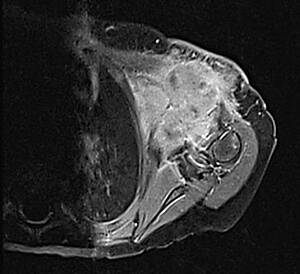

Rhabdoide Tumoren können in allen Geweben des Körpers entstehen. Am häufigsten betreffen Sie das Gehirn und das Rückenmark, die Nieren und die Leber, Hals-, Oberschenkel-, Brustwand- und anderer Weichgewebe (siehe Abb. 1a-c). Rhabdoide Tumoren des Gehirns werden auch als AT/RT („atypischer teratoider, rhabdoider Tumor“), solche der Nieren als RTK („rhabdoid tumor of the kidney“) und solche der Weichgewebe als MRT („malignant rhabdoid tumor“) bezeichnet.

Abb.1c: Rhabdoid-Tumor linke Schulter